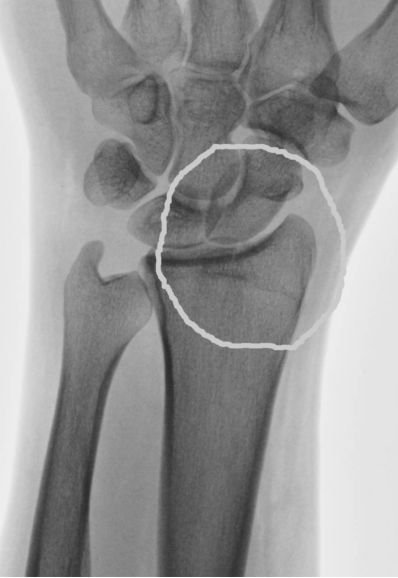

It didn't hurt to start with, then after an hour or so, it was sore, so I take a couple of nurofen tablets, still believeing that is just a sprain, only to find that by lunchtime I can't change gears or work the handbrake of the truck, so off to the hospital, only to find, after "they've" taken an xray that I've broken the top part of my left radius a.k.a radial styloid (I think that's what they called it anyway).